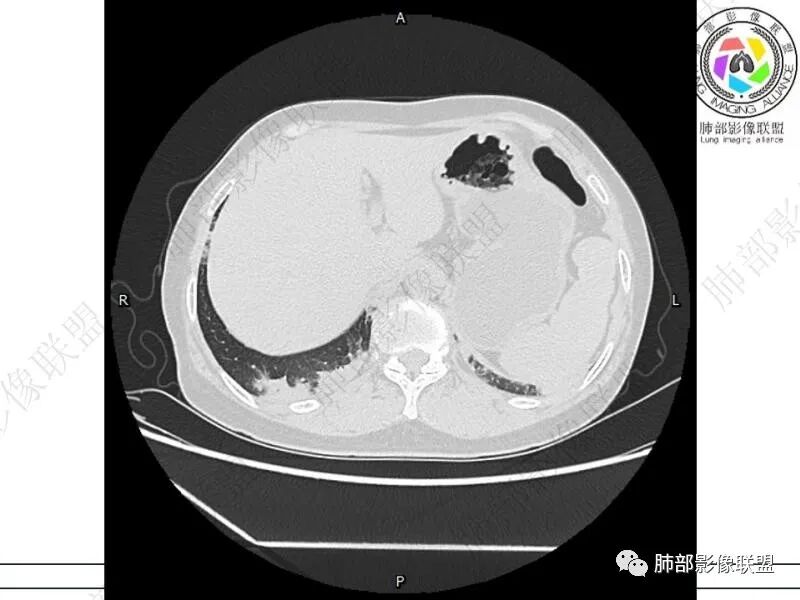

丽:双肺下叶胸膜下多发片状高密度影,边缘模糊不清,内可见支气管穿行,病变长轴平行于胸膜,考虑感染性病变,隐球菌

谢加平:结肠癌术后史,两肺胸膜下多发结节及斑块实变病灶,实边边界平直征(亚急性和慢性病变过程),双肺下叶后基底段胸膜下为甚,与胸膜平行特点,见支气管充气征,边缘模糊的GG0,首诊2022年11月18日肺部CT,与治疗11月28日对比,病灶未吸收,双肺下叶胸膜下病灶有侧向融合特点,综合分析符合炎性肉芽肿,隐球菌感染。

老年女性,结肠癌术后。两下肺胸膜下为主片状实变,右下肺短期复查融合且病灶长轴平行于胸膜,实变内可见支气管充气征,边缘磨玻璃晕,另两肺内胸膜下散在数枚小结节状、楔形实性灶。考虑感染性病变,隐球菌可能,鉴别肺转移。

2.影像特征:双肺胸膜下多发实性结节、磨玻璃影及实变影,胸膜下优势分布、晕征、胸膜下脂肪间隙存在,部分病灶边界平直征,有侧向融合趋势。